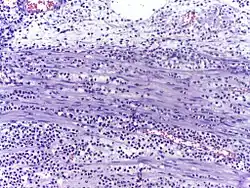

![]() Neutrophils with segmented nuclei surrounded by erythrocytes and platelets. Intra-cellular granules are visible in the cytoplasm (Giemsa stained). | |